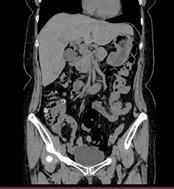

胸部CT 腹部CT

胸部CT画像               腹部CT画像